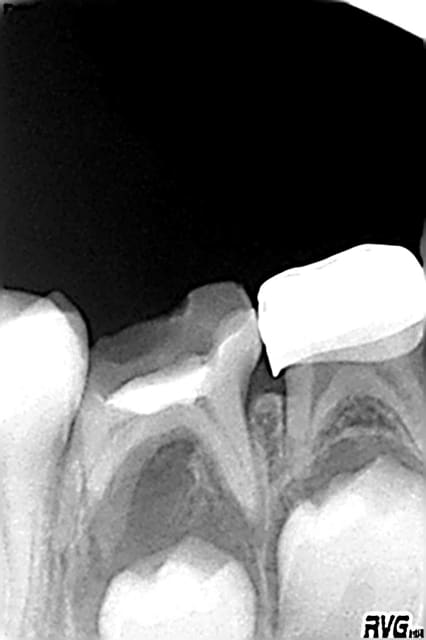

en 2006 ext de 75 et pose d'un mainteneur

en 2007 ext de 85 secteur où j'ai fait 2 erreurs:

1)ne pas mettre de couronne pedo en 2004 et me contenter d'un CVI(d'ou reprise de carie)

2)lors de l'extraction ne pas avoir mis de mainteneur d'espace au vu de la radio qui montrait 45 pas si loin...

et il manque de la place ,pas gd chose mais il manque!(photo en octobre et photo en janvier: pas de changement:c'est bloqué!)

direction odf(il faut bien qu'ils vivent les pauvres... si que les omni allaient leur enlever un cas de leurs pinces...)

mais comme quoi un mainteneur n'est pas inutile